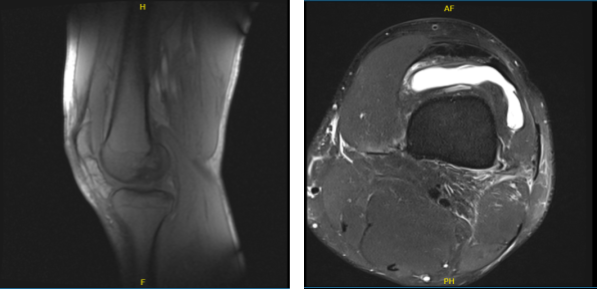

An MRI was done which showed tears of the medial and lateral meniscus as well as the ACL. We discussed treatment options and opted for surgical management at that time. He was taken for arthroscopic surgery a month back when repair of the meniscus root and the lateral meniscus was performed.

MRI of the left knee